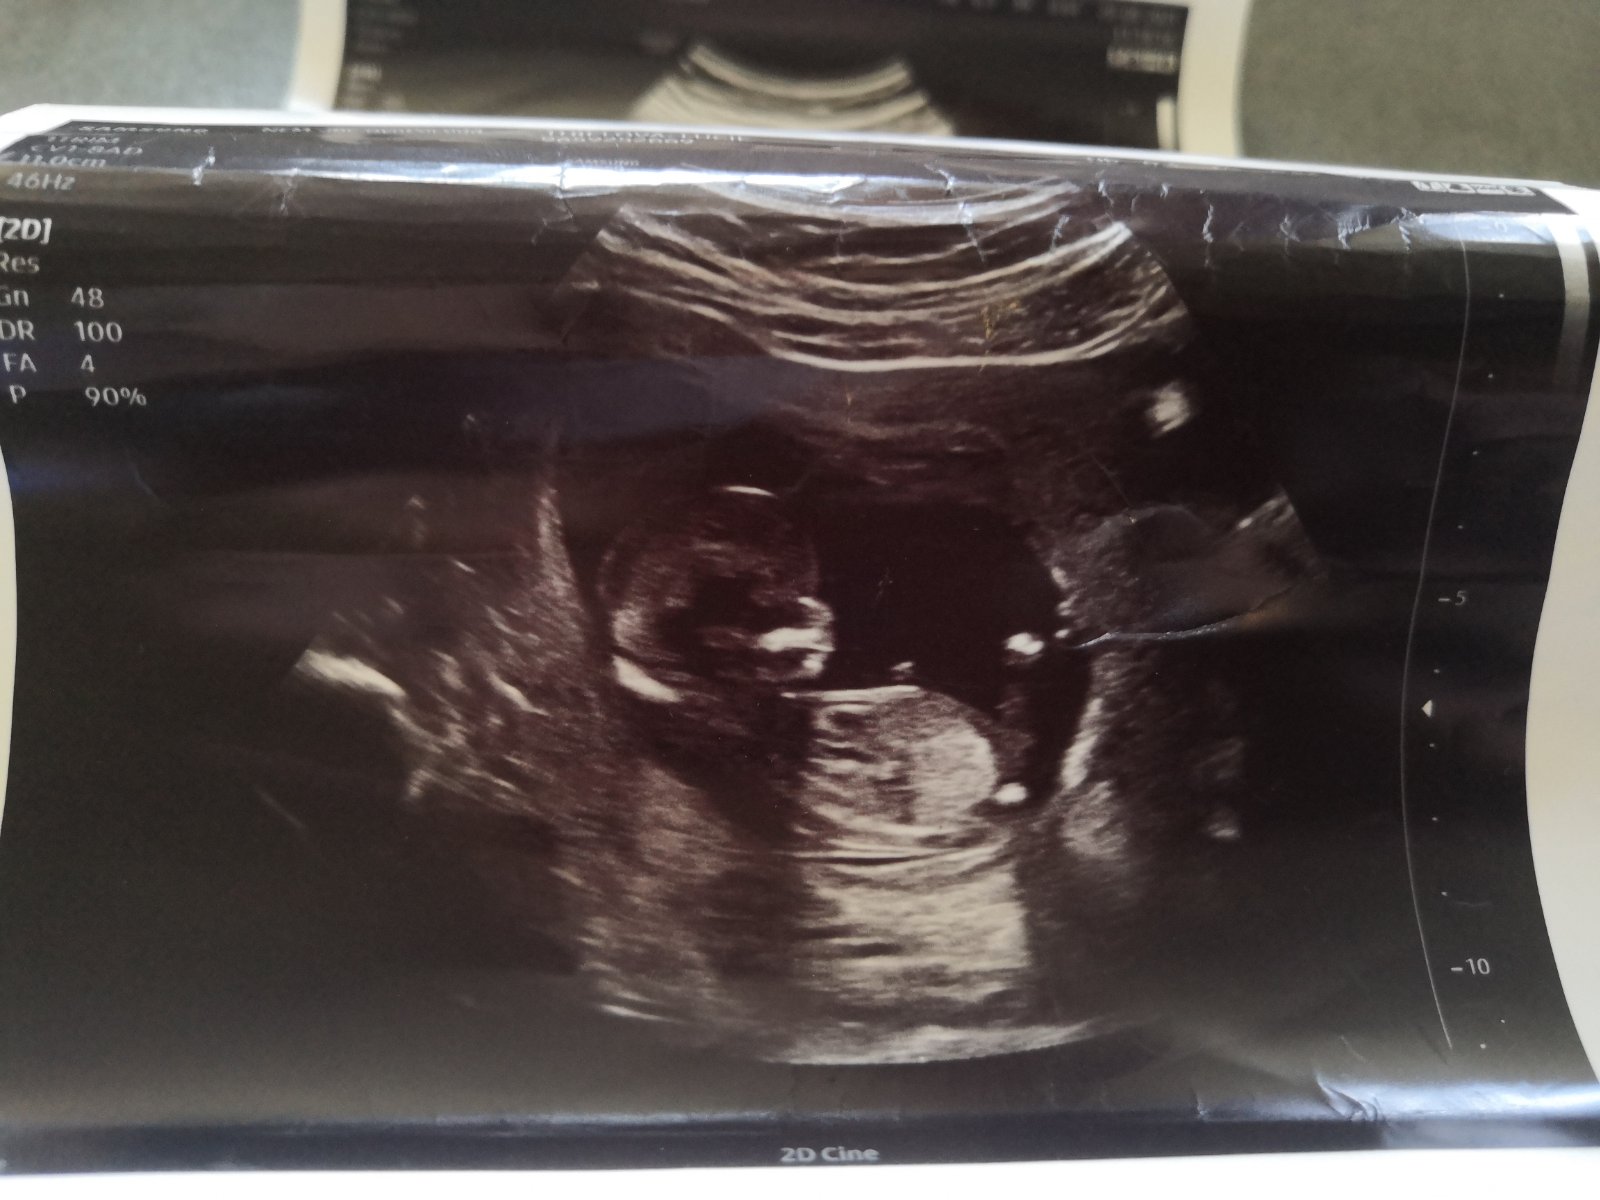

Pohlaví miminka. Co vidíte na ultrazvuku?

Ahoj holky, jen z mé zvědavosti a především netrpělivosti bych se chtěla zeptat i nestranných osob co vidí na ultrazvuku za pohlaví. Respektivě, co si dokážete odhadnout na základě pohlavního hrbolku. 🙈😅 Je to fotka z prvního screeningu, kde nás pan doktor řekl, že těžko říci, je to má tak půl na půl.

Ahoj holky, tak nastal den D, kdy by se nám to naše malé babby mohlo ukázat. Od rána jsem nervózní a vlastně ani nevím proč a z čeho 😂😂 aby té nervozity nebylo málo, tak už hodinu čekám v čekárně (a to jsem jsem objednaná). Takže jsem ve finále napnutá jak kšandy ještě víc. Závěr tedy je, poslední šance na přihazování sázek a budeme doufat, že se to krásné ukáže. 🙏

Tak vítězna skupina je, ta která tvrdila holcicku.

Paní doktorka neviděla ani kuličky a ani pindíka, ba naopak dle ní viděl krásne pipinu. ♥️♥️